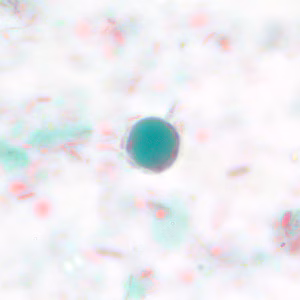

Case #228 – May, 2008

Within a week of returning from a conference in Mexico, a 28-year-old woman presented to her primary care physician with cramps, abdominal pain, gas and diarrhea. A routine Ova and Parasite (O&P) examination was performed on stool specimens. Figures A–F show objects observed on a trichrome-stained slide prepared from the stool. All images were taken at 1000x oil magnification. The objects in Figures A–C measured 12 micrometers. The objects in Figures D and E averaged 10 micrometers. The object in Figure F measured 12 micrometers in diameter. What is your diagnosis? Based on what criteria?

Figure C